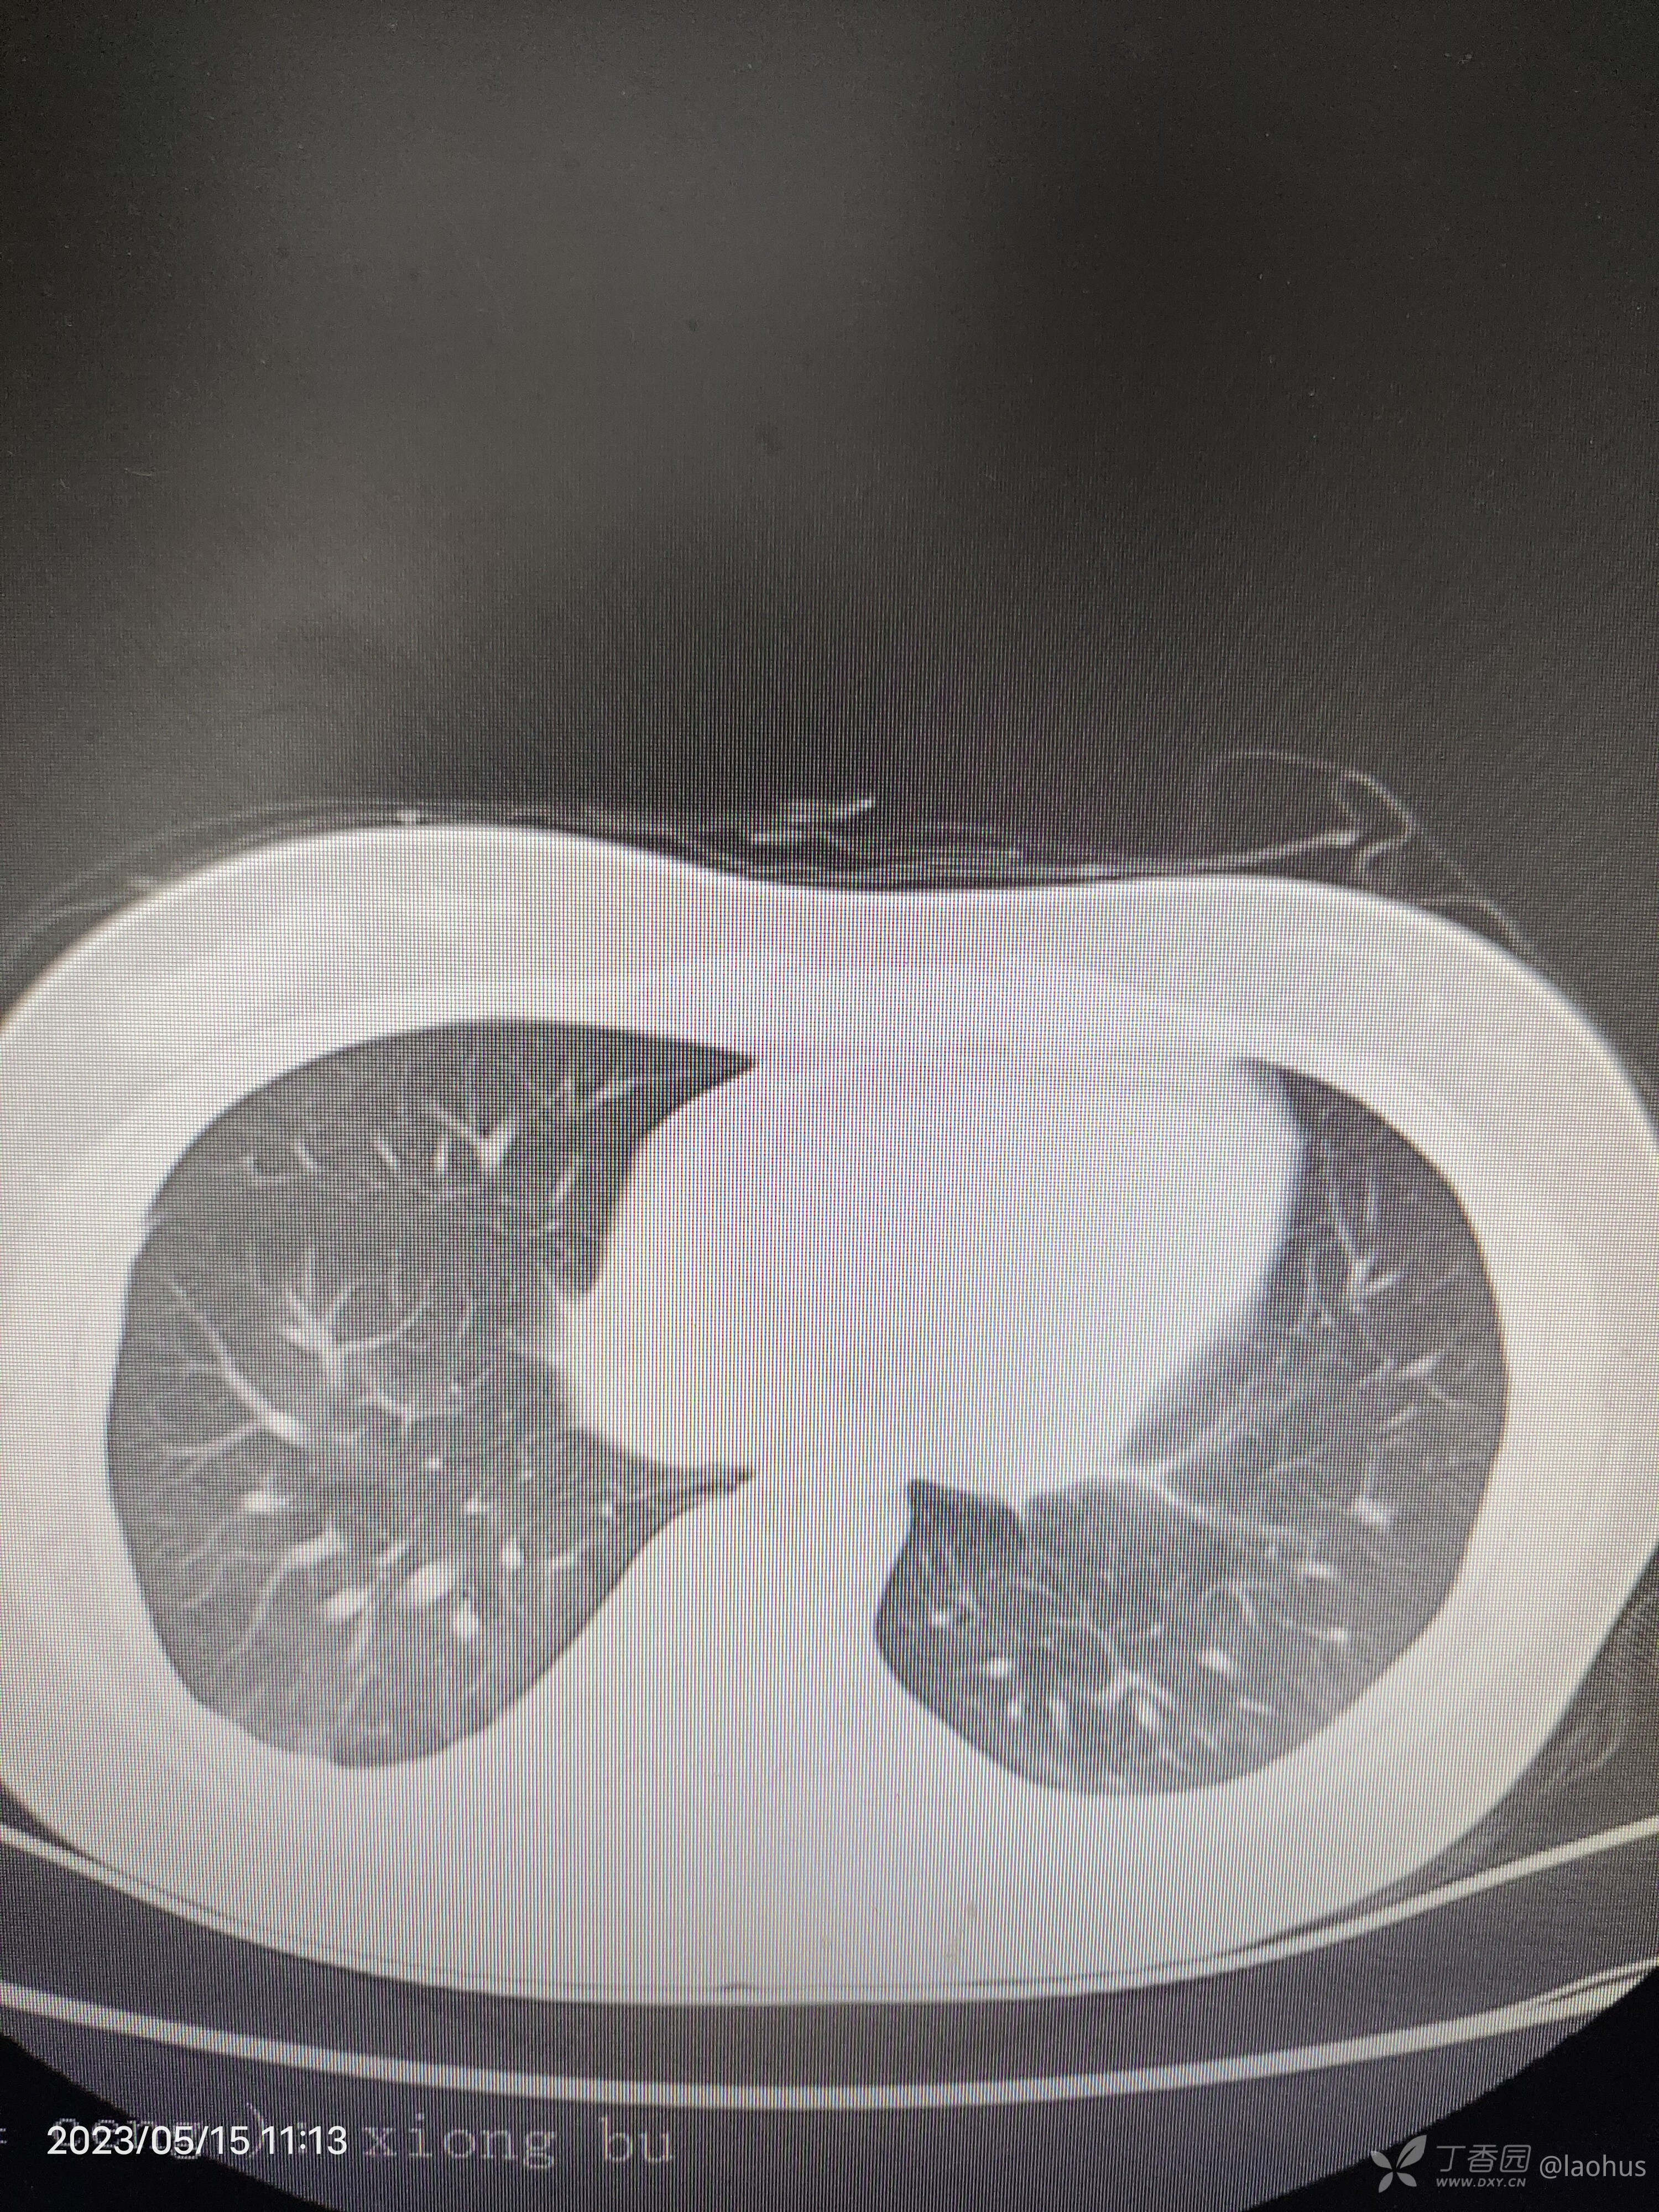

第三天CT